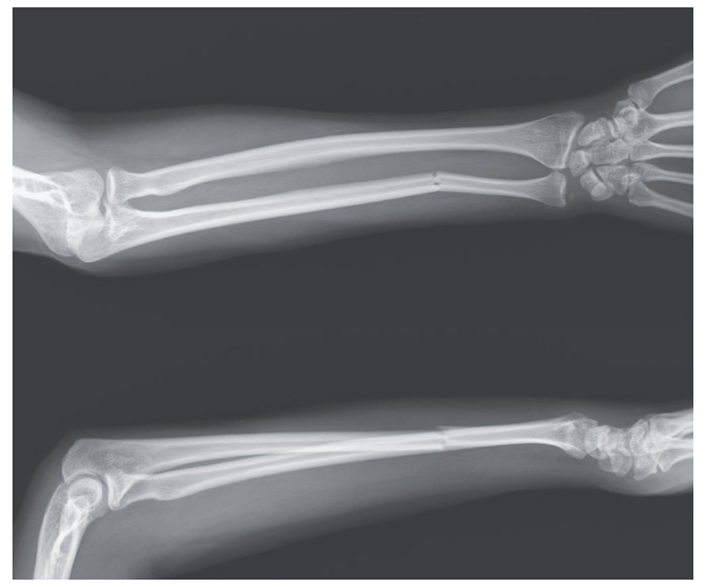

60歳の左利きの女性。パートナーに野球バットで殴られ、手で防御したところ左前腕に痛みが出現し救急外来受診。 身体所見としては左前腕に腫脹を認め、同部位は圧痛があ…